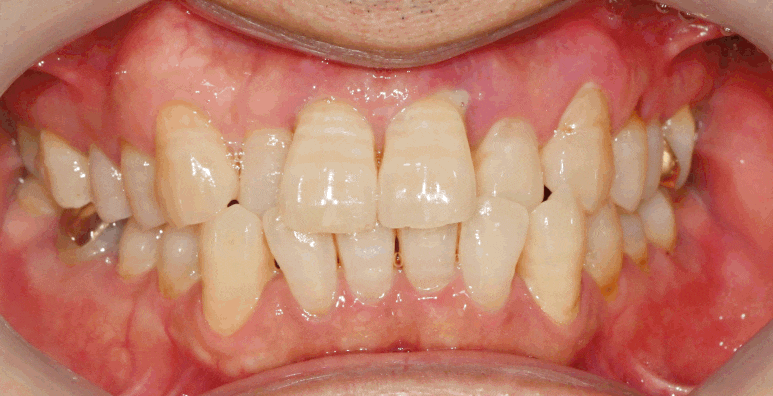

"앞니가 틀어져서 보기 안 예뻐요."

위와 같은 말씀을 하며

보라매 치과 에 찾아오셨습니다.

우선 윗니가 아랫니의 1/3을 덮어야

바람직한 교합관계인데,

이 케이스에서는 양측 윗니의 두 번째인

상악 측절치가 안으로 들어가

아래 앞니 두 번째와 반대로 자리하고 있습니다.

그렇기 때문에

위아래 치열이 틀어져

심미성도 떨어지고

평소 치태나 구강관리에도

어려움이 있으셨을듯합니다.